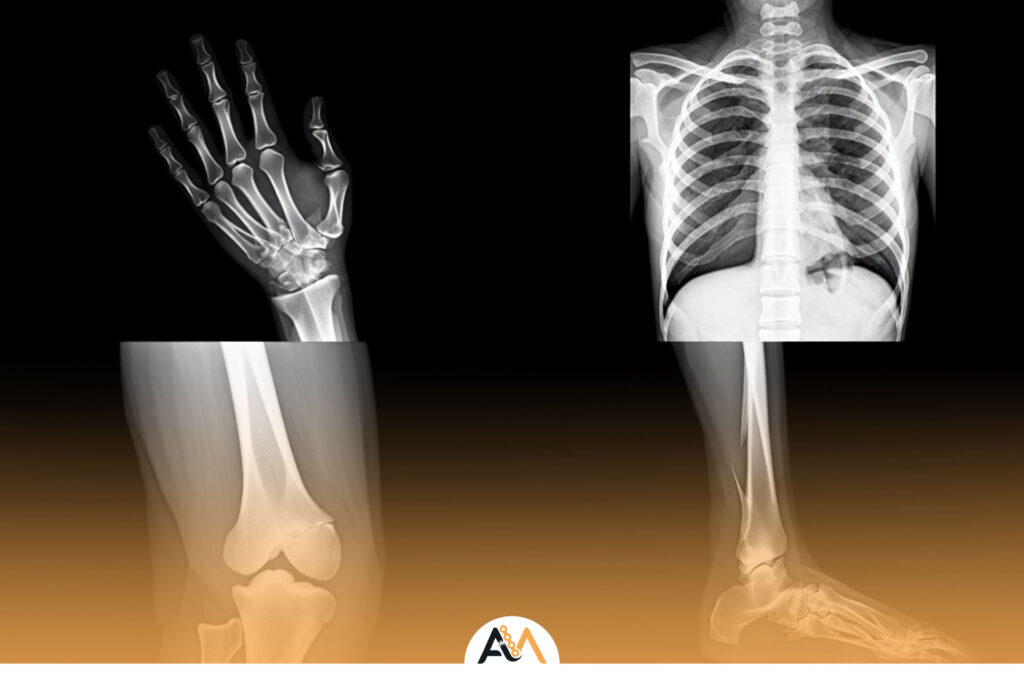

نشانه های جوش خوردن استخوان | علائم بهبود شکستگی و روند ترمیم استخوان

شکستگی استخوان یکی از شایعترین آسیبهایی است که ممکن است در هر سنی رخ دهد و روند بهبود آن نیاز به مراقبت دقیق دارد. آشنایی با نشانه های جوش خوردن استخوان به بیماران و خانوادهها کمک میکند تا بتوانند وضعیت ترمیم را بهتر درک کرده و در صورت نیاز، اقدامات پزشکی لازم را انجام دهند. […]